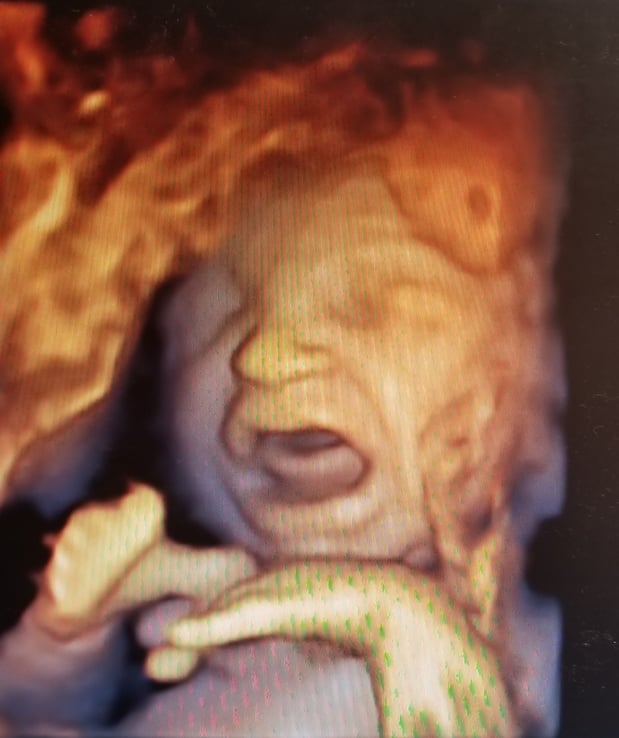

Tasha Crump, is registered by the American Registry of Diagnostic Medical Sonographers (ARDMS) and have over 18 years experience in medical diagnostic sonography specializing in Maternal Fetal Medicine. She is a highly proficient in the art of 3D 4D ultrasound. Tasha has practiced and trained in NYC's top ranked hospitals including Columbia Presbyterian. At Love at First Sight Imaging Studio you'll be in a very comfortable and calming atmosphere for you and your family to bond with your baby. We have state of the art equipment with HD Live to image unbelievably realistic views of your baby. You will fall in Love at First Sight.